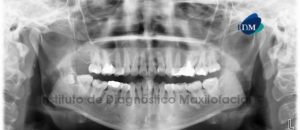

Paciente femenino, 23 años de edad es referido al Instituto de Diagnóstico Maxilofacial (IDM) para realizar su estudio previo al tratamiento de ortodoncia.A la evaluación